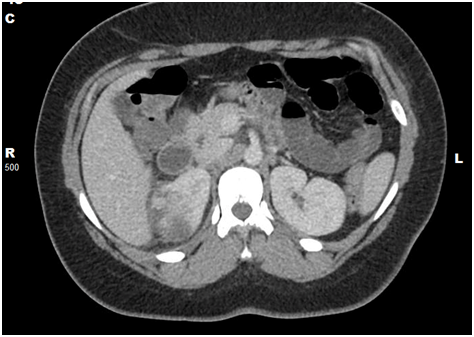

Laboratory findings were remarkable for white cell count of 11,100 cells/microliter (mcL) .Urine culture from ED visit one day prior showed Escherichia coli>100,000 colony forming units /ml (CFU/ml), which was sensitive to all tested antibiotics except ampicillin, trimethoprim/sulfamethoxazole and gentamicin. Intravenous (IV) Contrast enhanced Computed Tomography (CT) scan of the abdomen and pelvis showed findings consistent with acute pyelonephritis on the left side with an area of of low-attenuation in the upper pole, measuring up to 3.5 cm, which may represent a developing abscess (Figure 1). Patient was given ceftriaxone IV 1 gm every 24 hours and IV hydration with normal saline. She also received analgesics for pain control. A renal ultrasound(US) of the abdomen and pelvis was done 36 hours after admission, which showed no change in the appearance of the hypoechoic focal area in the upper pole of the left kidney consistent with focal pyelonephritis. The patient had an uneventful recovery and was discharged home on oral Ciprofloxacin to complete a total of 21 days of antibiotic treatment.

Figure 1 Computed tomographic image with intravenous contrast of abdomen and pelvis of case 1 showing left renal pyelonephritis with 3.5 cm area of hypoenhancement and adjacent stranding (acute lobar nephronia).